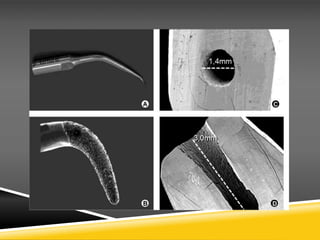

Root-end resection

The main reason for a surgical approach to an endodontic problem is to remove

extraradicular bacteria and other contaminants causing clinical symptoms. However,

the anatomy of the root apex is complicated, with multiple portals of exit and

accessory canals.

Indeed, the presence of apical ramifications may be a major contributing factor

towards the occurrence of refractory PRD.63 Microbial biofilms form on the root

apex and these penetrate the dentinal tubules. Thus, however effective the apical

curettage has been, there

is a potential for recontamination, maintained inflammation, and ultimately surgical

failure unless the root apex is removed. It is generally accepted that an apical

resection of

3 mm will remove the majority, if not all, of these potential problem areas. This

resection will additionally permit thorough inspection of the root canal, preparation

of a cavity to encompass the canal shape and placement of a retrograde seal.

the angle of resection should be as close to horizontal as possible (i.e. at right

angles to

the long axis of the tooth). This exposes a minimal number of dentine tubules,

thereby reducing apical leakage and providing the best potential for healing